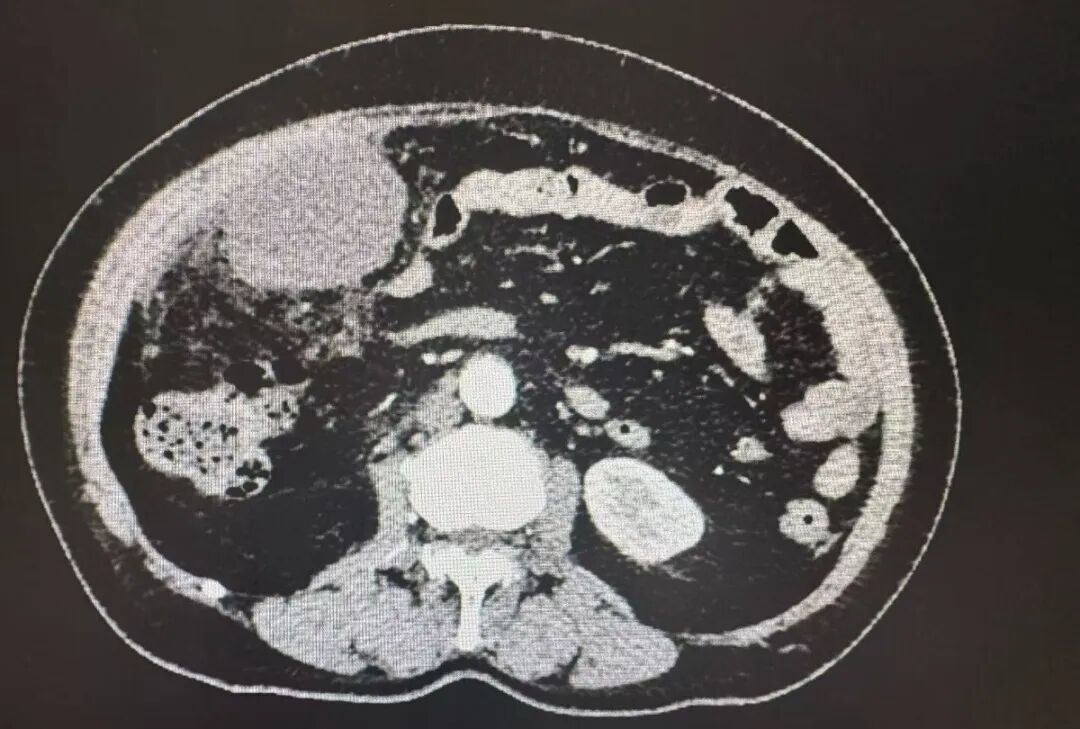

急诊检查结果显示,白细胞数值是正常值的近四倍,CT示右下腹一团糟,阑尾不仅化脓穿孔,还形成了一个大脓肿,脓液已经扩散到整个腹腔,医生考虑急性坏疽性阑尾炎伴穿孔,弥漫性腹膜炎,阑尾周围脓肿。

与家属充分沟通后,急诊腹腔镜微创手术火速进行。术中景象印证了术前的判断,当镜头探入腹腔,腹腔内里积了不少黄褐色脓液,肠子、子宫、大网膜等因为严重的炎症粘在一起。

普外科手术团队副主任医师宋书亚、医师杨慧斌就像在错综复杂的雷区里作业,小心翼翼地分离粘连的组织,最终在右侧腹腔的不同位置,找到了三个隐藏的脓肿,先后抽出了500毫升的脓液和坏死组织。